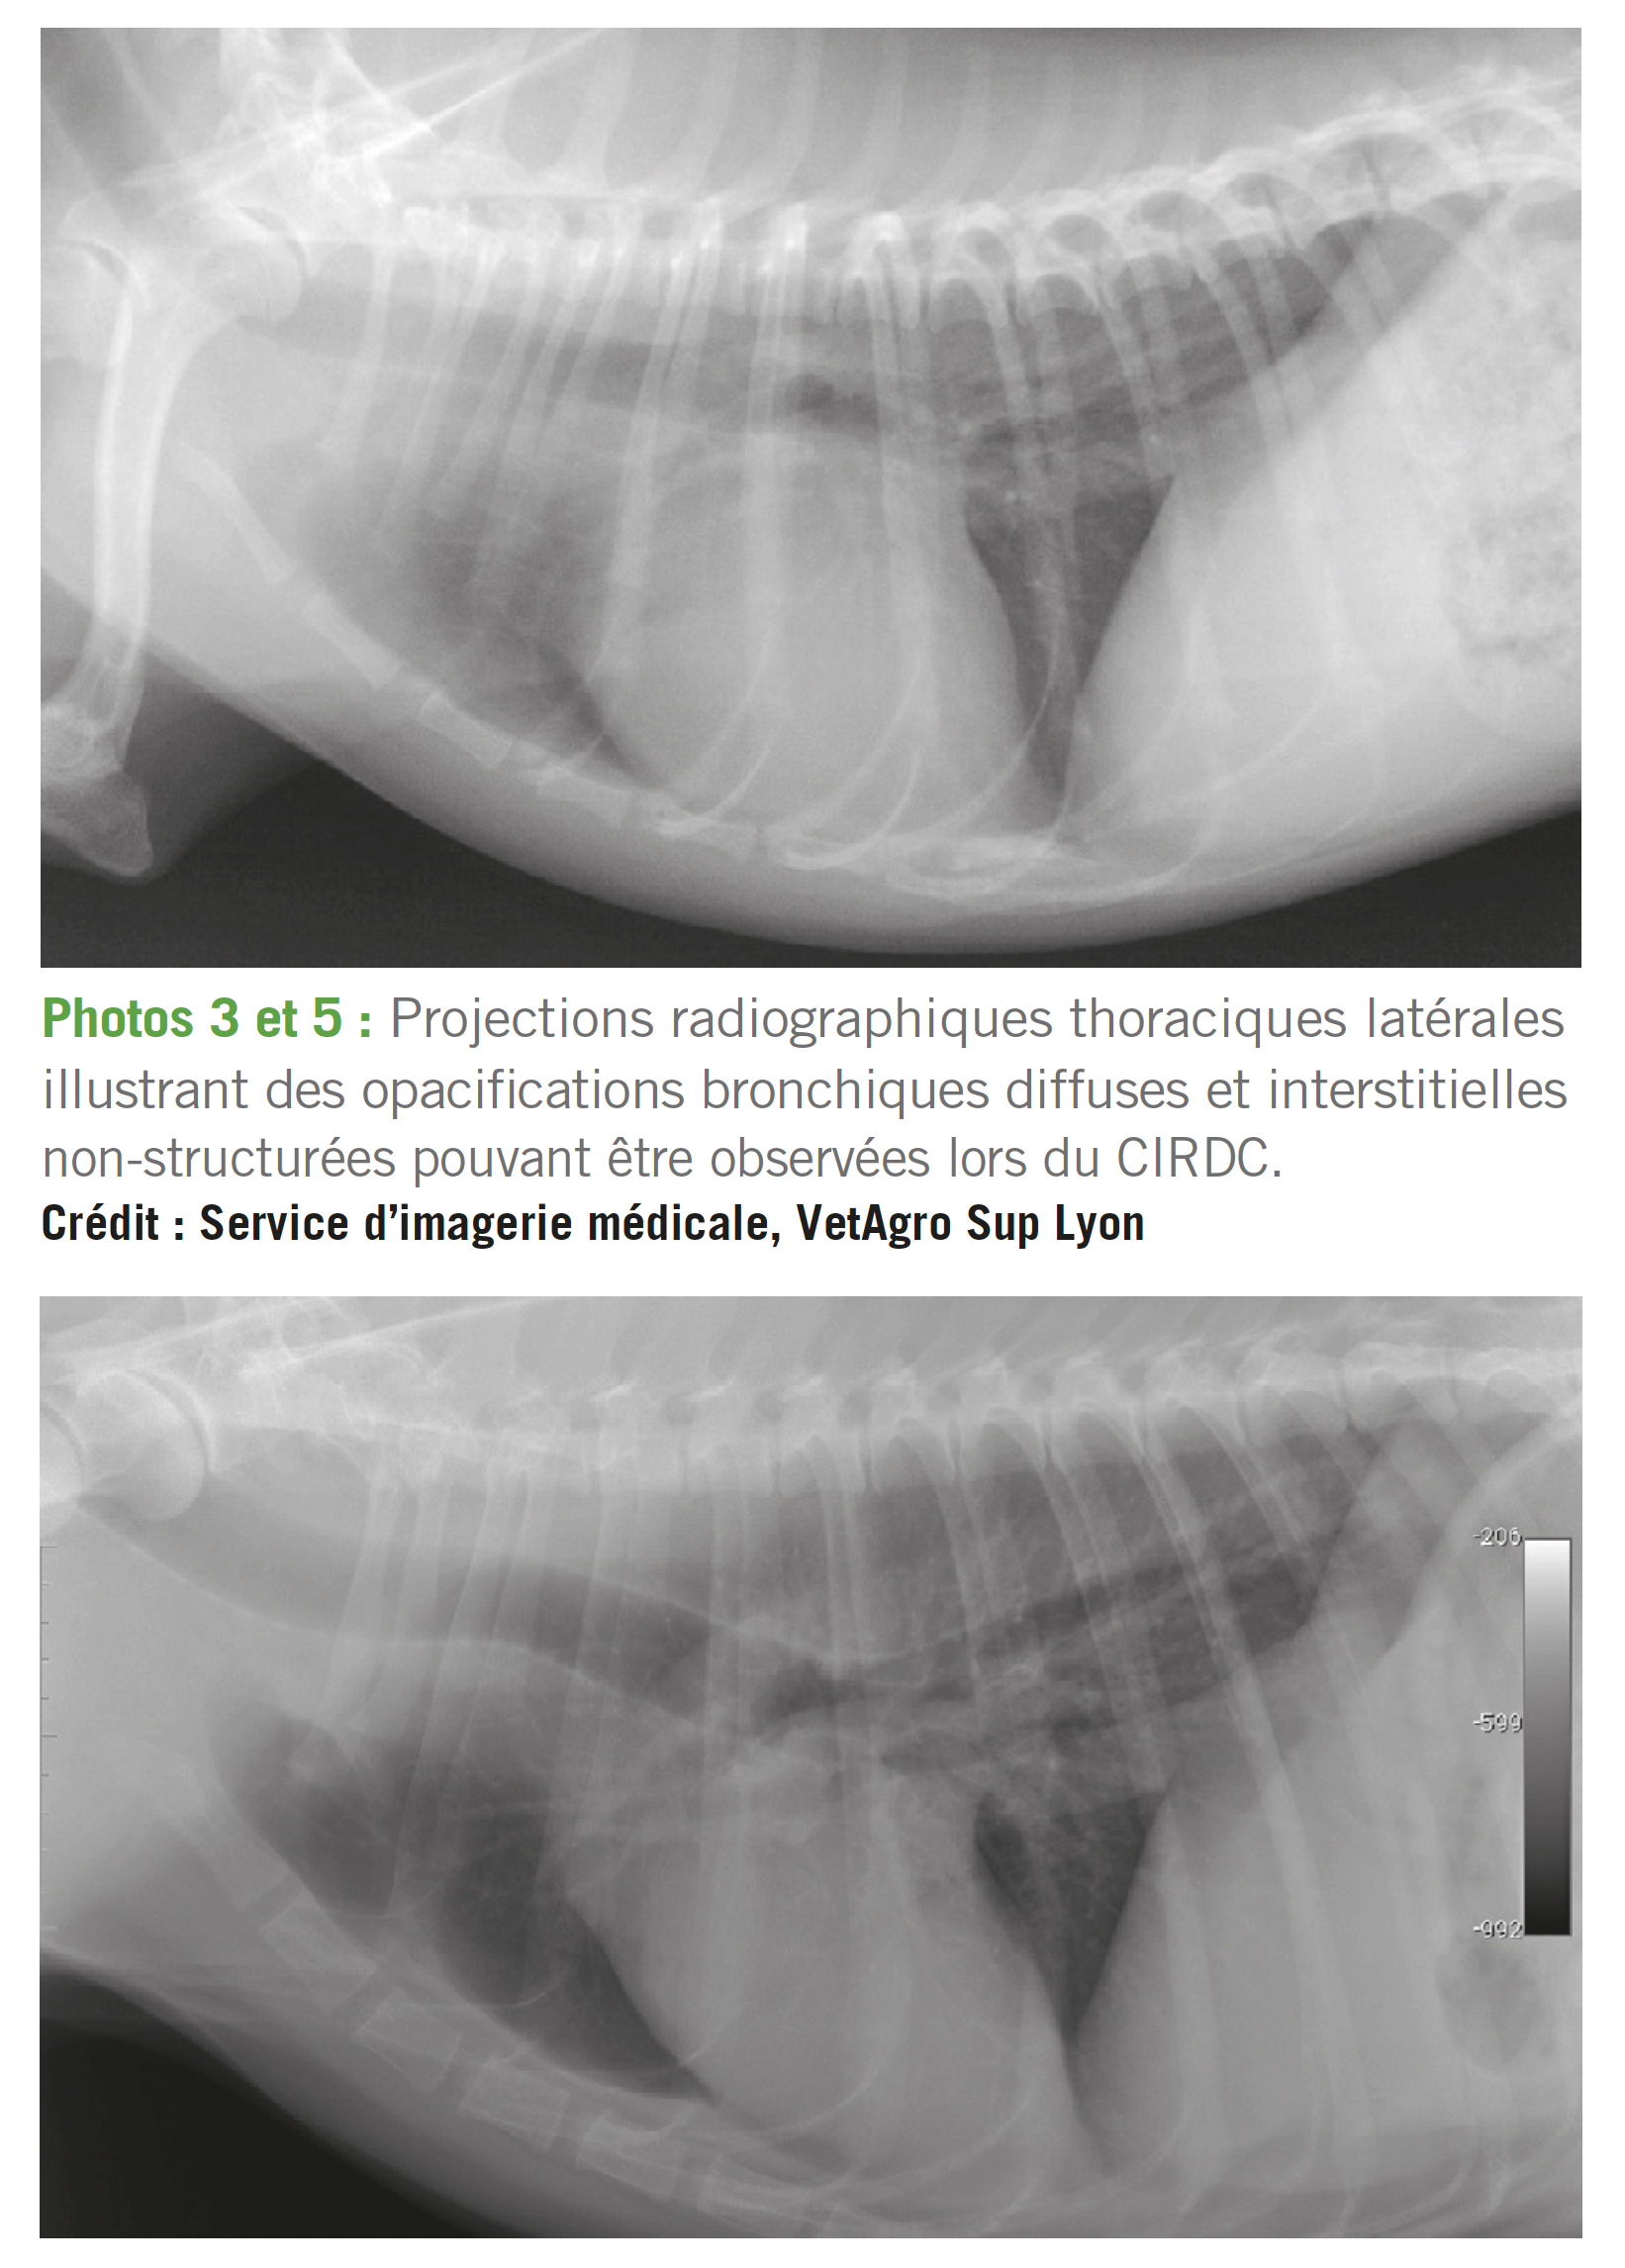

En l'absence de réponse rapide aux antitussifs, anti-inflammatoires et antibiotiques, et en cas de dégradation générale et respiratoire (détresse respiratoire), des radiographies thoraciques peuvent devenir utiles, afin de préciser le type et l'étendue des lésions (cf. photos 2 à 5). Une opacification radiographique bronchique diffuse est rencontrée dans virtuellement 100 % des trachéo-bronchites infectieuses canines 1-4,14.

Cependant, cette anomalie n'est pas spécifique et l'intérêt de la radiographie thoracique s'explique principalement dans ce contexte par la nécessité de rechercher des lésions qui aggravent ou entretiennent la toux (foyers alvéolaires notamment).